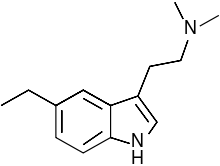

| 5-Ethyl-DMT | artificial | 5-CH2CH3 | CH3 | CH3 | 5-ethyl-N,N-dimethyltryptamine | 171783-25-8 |